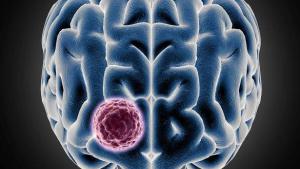

في اختراق طبي جديد، استطاع علماء من جامعة مكاجيل الكندية، تحديد «جين» تم اختصاره بحروف «PDGFRA»، يساعد في نمو سرطان الدماغ المميت «ورم الأرومي الدبقي»، أحد أنواع السرطان العنيفة الذي يستهدف الدماغ أو الحبل الشوكي، ويموت المريض بعد ثلاث سنوات من الإصابة به، خاصة من المراهقين والشباب، ما يسهم في إيجاد علاجات محددة تستهدف هذا «الجين».

وباستخدام تقنيات جديدة تقيس مستويات كل «جين» في آلاف الخلايا الفردية، اكتشف الباحثون أن الورم ينشأ في نوع معين من الخلايا الجذعية العصبية، واستعانوا بخلية واحدة لإنشاء «أطلس للدماغ» لتحديد مئات أنواع الخلايا وخصائصها.